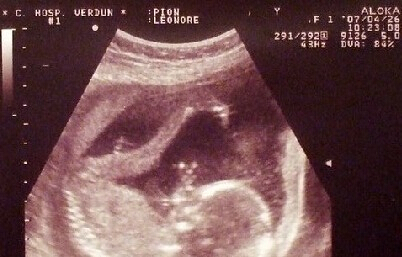

(怀孕检测示意图)

新世纪女子医院医生指出,很安全、很有效的检查方法便是到医院进行B超检查,可以迅速帮您检查出是否怀孕,还能检查出是否存在异常情况。常用的检查方法主要有以下几种:

4、超声波检测:有些女性误认为怀孕就能够用超声波(B超)检查,实际上需要等到怀孕5周左右,才能够看到子宫中是否有囊胚存留。超声波检测不仅可以检测囊胚的成长,更可以检验是否存在宫外孕的可能。